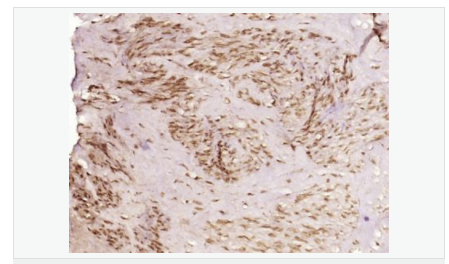

交叉反應(yīng):Human,Mouse,Rat(predicted:Dog,Pig,Cow,Horse,Rabbit,Sheep) 推薦應(yīng)用:IHC-P,IHC-F,ICC,IF

交叉反應(yīng):Human,Mouse,Rat(predicted:Dog,Pig,Cow,Horse,Rabbit,Sheep) 推薦應(yīng)用:IHC-P,IHC-F,ICC,IF

| 產(chǎn)品應(yīng)用 | IHC-P=1:100-500 IHC-F=1:100-500 ICC=1:100-500 IF=1:100-500 (石蠟切片需做抗原修復(fù)) not yet tested in other applications. optimal dilutions/concentrations should be determined by the end user. |

| 細(xì)胞定位 | 細(xì)胞核 細(xì)胞漿 |

| 產(chǎn)品介紹 | This gene encodes a member of the TET family of RNA-binding proteins. The encoded protein plays a role in RNA polymerase II gene transcription as a component of a distinct subset of multi-subunit transcription initiation factor TFIID complexes. Translocations involving this gene play a role in acute leukemia and extraskeletal myxoid chondrosarcoma, and mutations in this gene may play a role in amyotrophic lateral sclerosis. Alternatively spliced transcript variants encoding multiple isoforms have been observed for this gene. [provided by RefSeq, May 2012] Function: RNA and ssDNA-binding protein that may play specific roles during transcription initiation at distinct promoters. Can enter the preinitiation complex together with the RNA polymerase II (Pol II). Subcellular Location: Nucleus. Cytoplasm. Shuttles from the nucleus to the cytoplasm. Tissue Specificity: Ubiquitous. Observed in all fetal and adult tissues. Post-translational modifications: Dimethylated by PRMT1 at Arg-206 to asymmetric dimethylarginine. The methylation may favor nuclear localization and positive regulation of TAF15 transcriptional activity. Phosphorylated upon DNA damage, probably by ATM or ATR. DISEASE: Note=A chromosomal aberration involving TAF15/TAF2N is found in a form of extraskeletal myxoid chondrosarcomas (EMC). Translocation t(9;17)(q22;q11) with NR4A3. Similarity: Belongs to the RRM TET family. Contains 1 RanBP2-type zinc finger. Contains 1 RRM (RNA recognition motif) domain. SWISS: Q92804 Gene ID: 8148 Database links: Entrez Gene: 8148 Human Entrez Gene: 70439 Mouse Omim: 601574 Human SwissProt: Q92804 Human Unigene: 402752 Human Unigene: 181050 Mouse Unigene: 72554 Rat Important Note: This product as supplied is intended for research use only, not for use in human, therapeutic or diagnostic applications. |